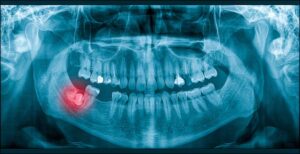

Személyes konzultáció, röntgenfelvételek, 3D lenyomatvétel, az eredményszimuláció bemutatása és fotódokumentáció.

De Doktornő, tényleg fontos a röntgen?

„Tényleg szükség van röntgenre? Nem elég, amit szabad szemmel látunk?” A válaszunk határozott NEM – és eláruljuk, miért nálunk van